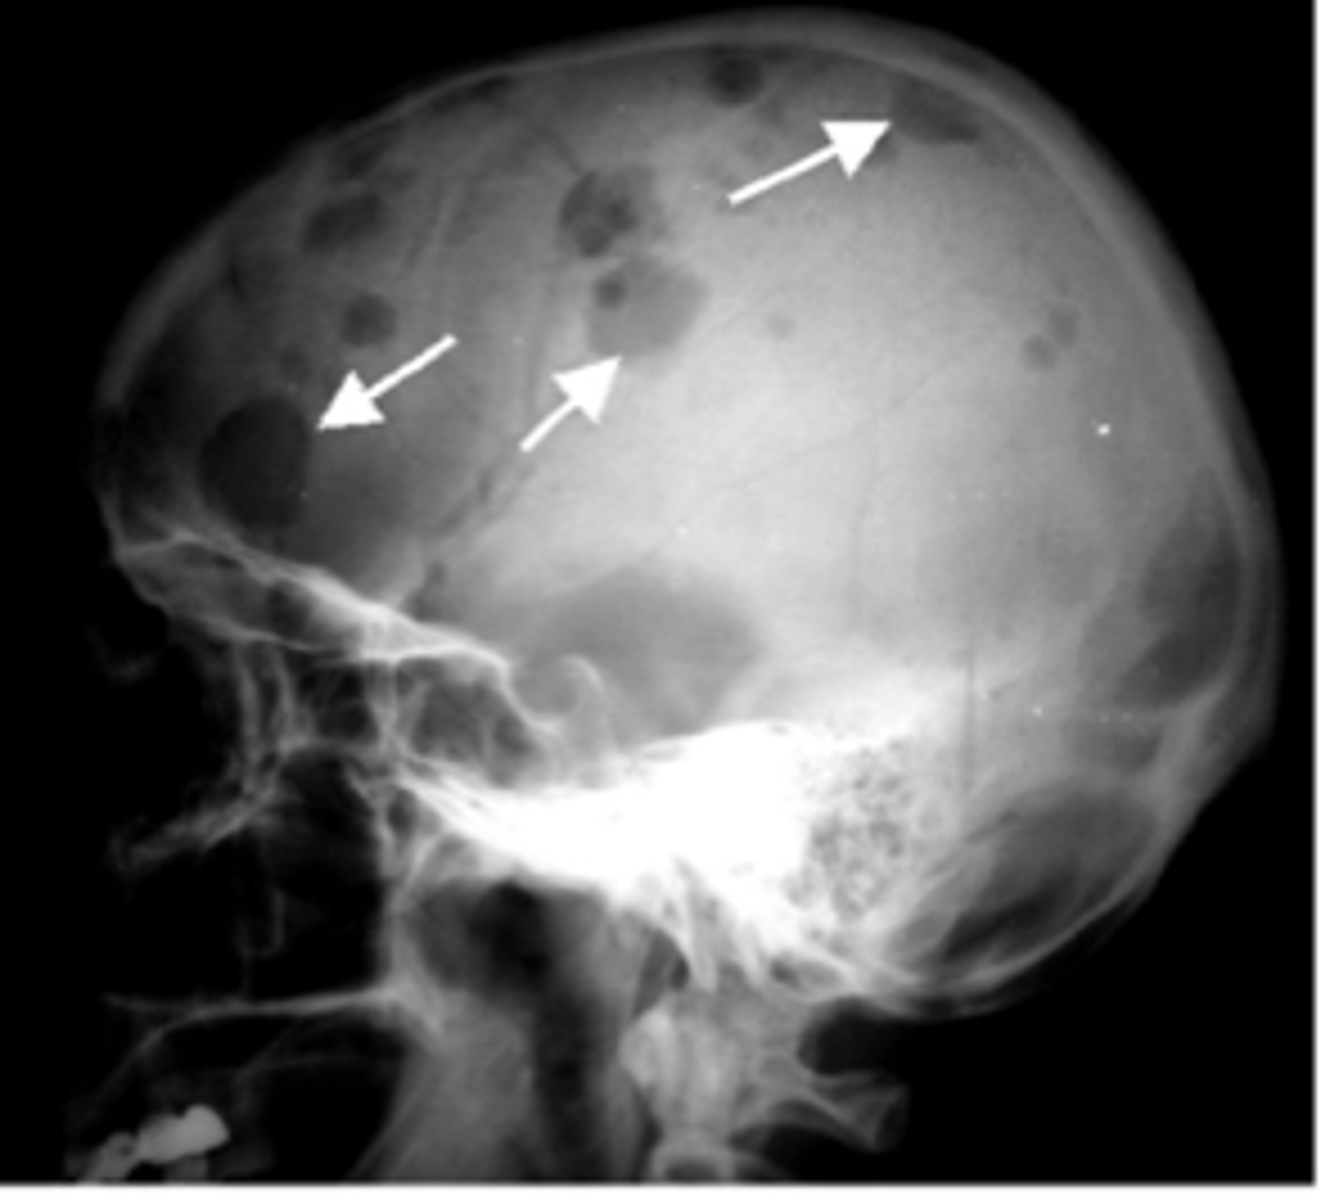

multiple myeloma

malignancy of bone in adults

solitary plasmacytoma- often seen as a soap-bubbly, expansile lesion in spine or pelvis

punched out lytic lesions- throughout axial and proximal appendicular skeleton